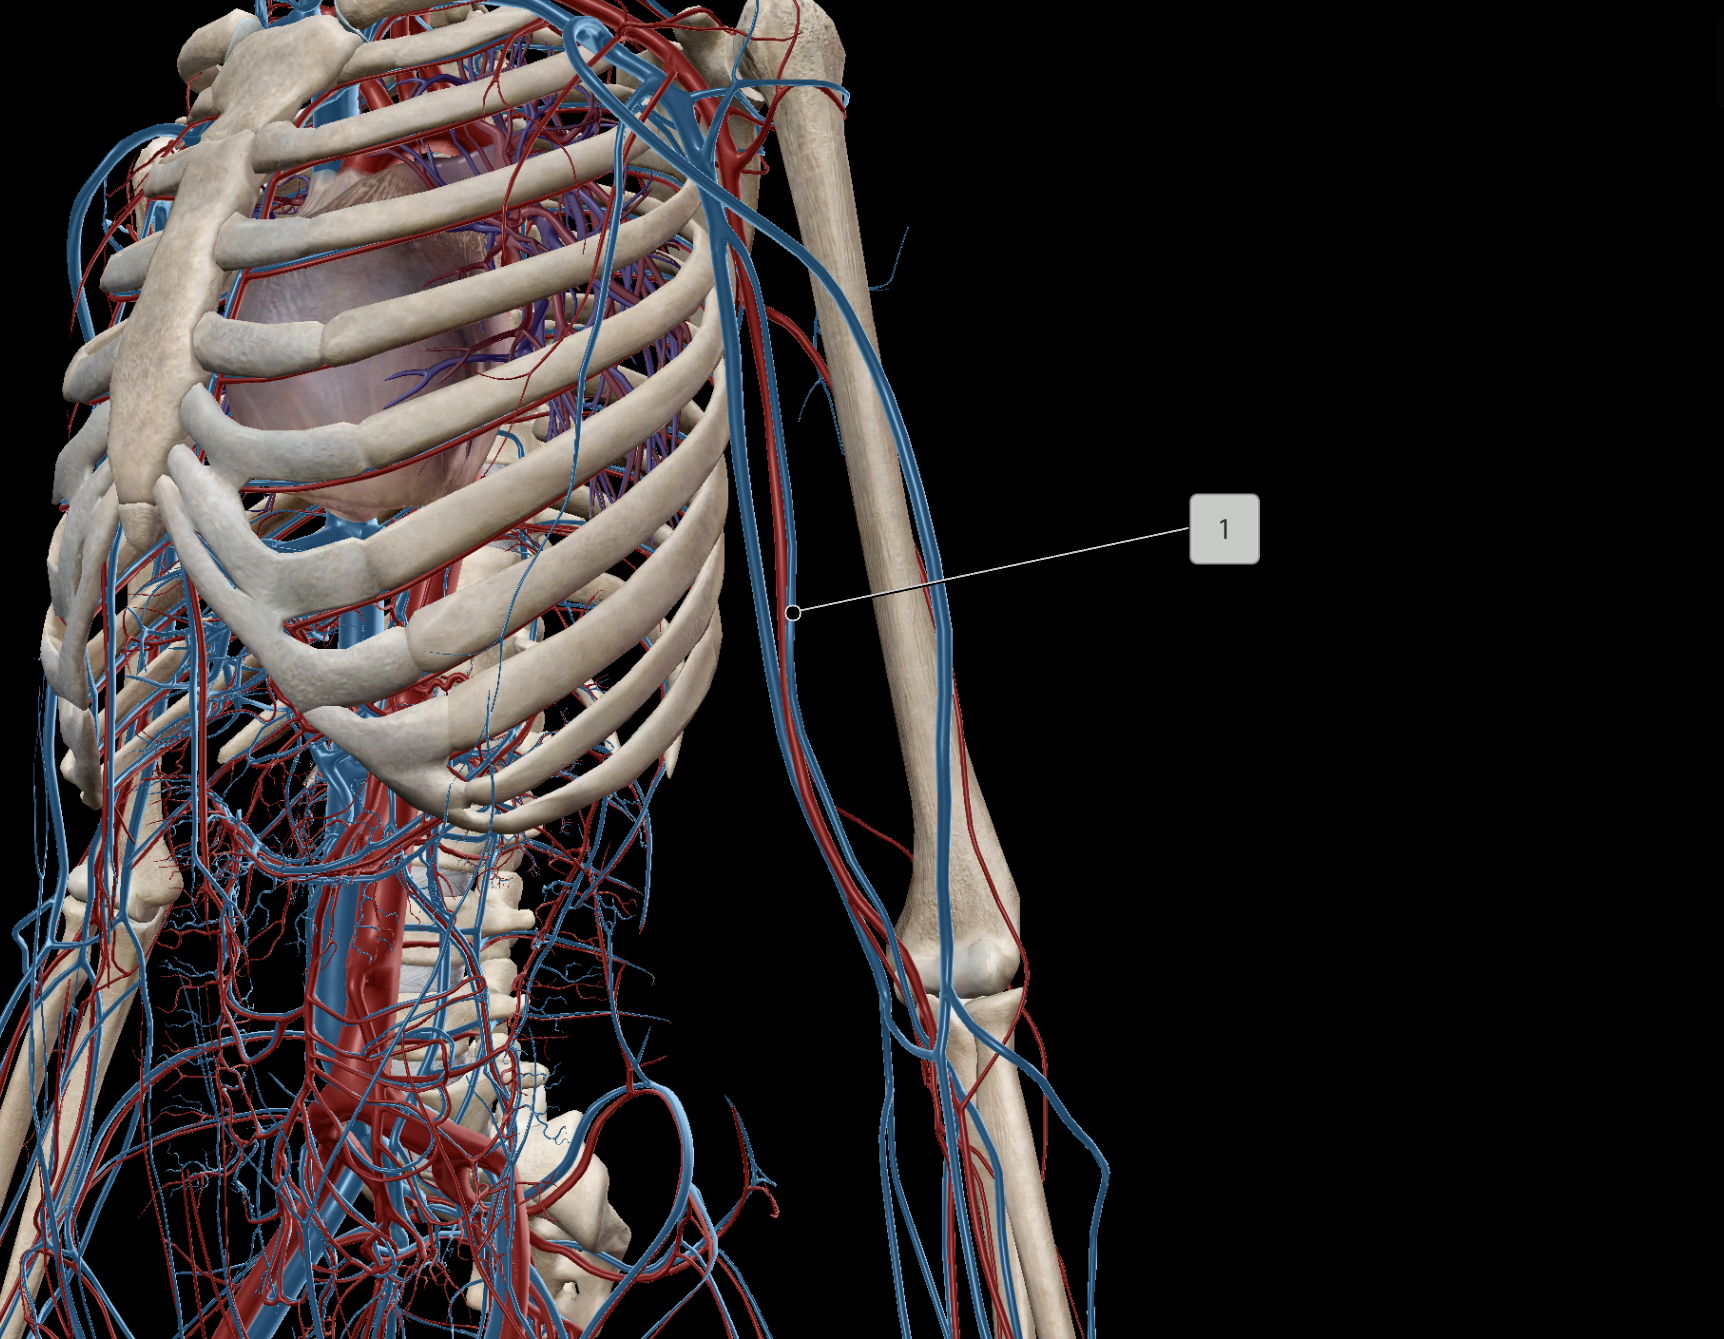

Brachial Artery

Subclavian Artery

Axillary Artery

Brachial Vein

Axillary Vein

Subclavian Vein